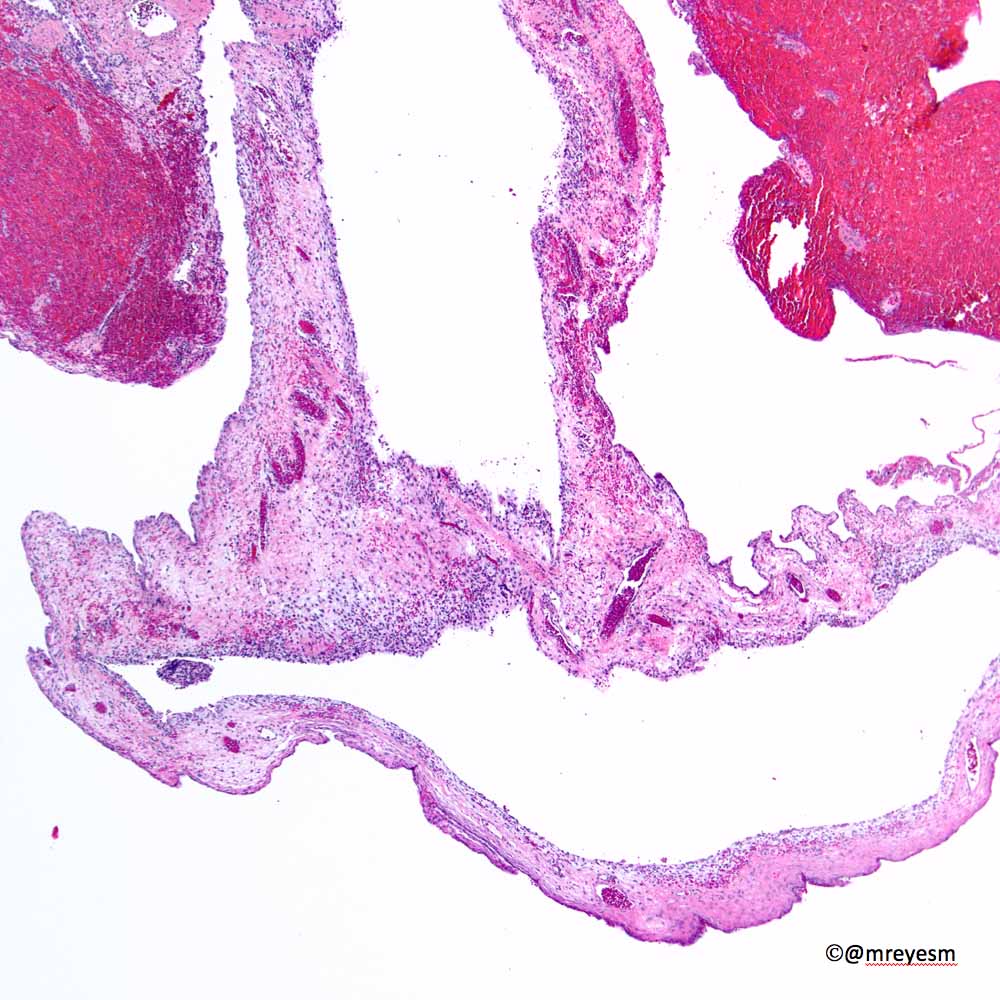

@thoracicpath

Charles Leduc, MD

4 years

Thanks to all who engaged! Although uncommon, chronic LCH can lead to severe secondary pulmonary HTN which is what we see here. A spectrum of arterial lesions, including plexiform, dilatation, and medial hypertrophy. Wishing the patient a new lease on life with new lungs!

!

Explants from woman in her mid 40s. Clinical history on req: pulmonary hypertension. IHC is CD1a. Unifying diagnosis?